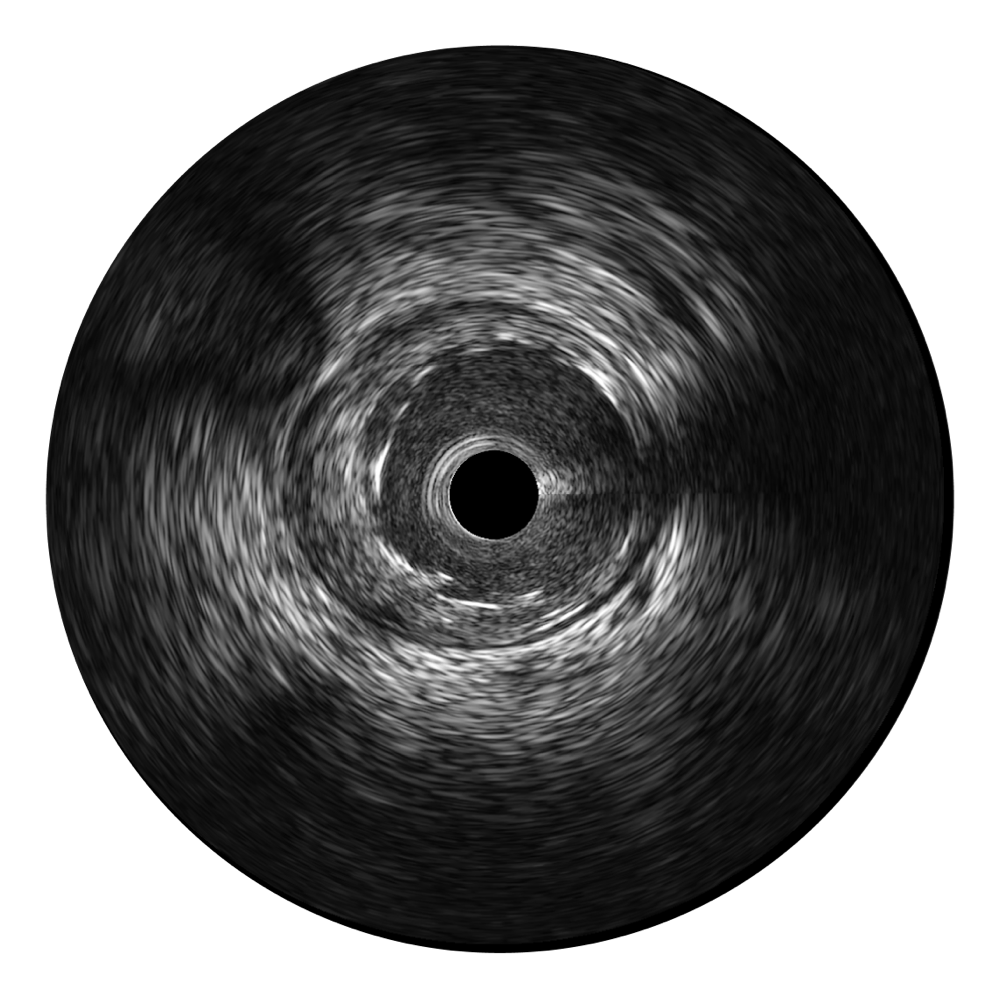

• 米兰官方网站宽频IVUS图像

对比传统IVUS导管成像,米兰官方网站宽频IVUS图像的近场支架梁显影更细腻,远场中膜外血管仍清晰可辨,兼顾远中近,兼顾分辨力与穿透深度